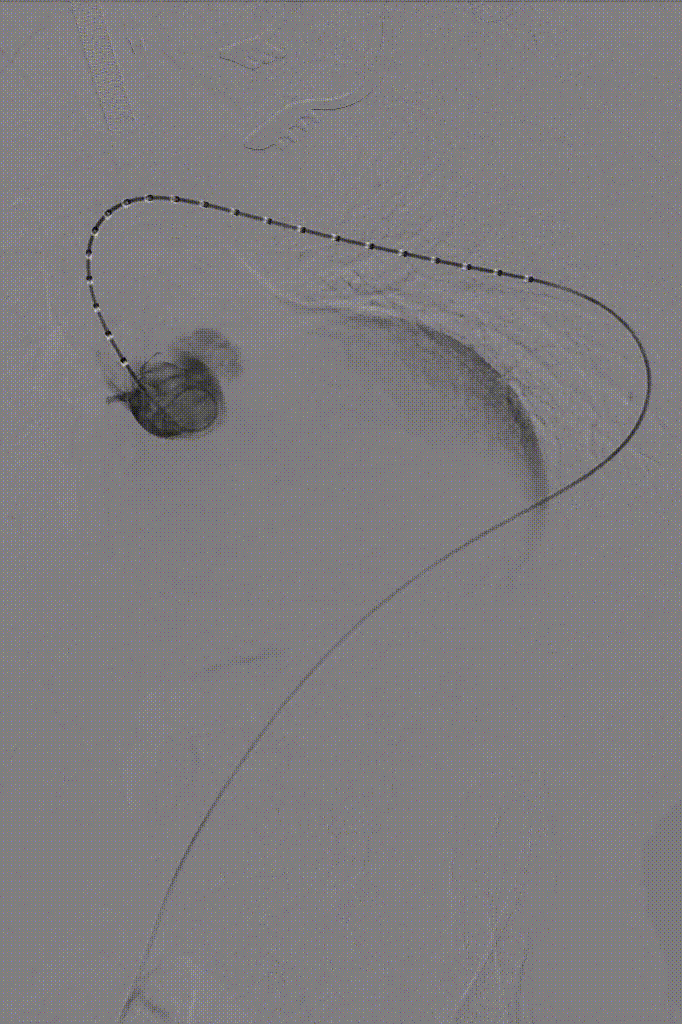

第七步、最终造影,关闭手术切口。

gore医疗怎么样「胸有乾坤」国际首例 微创杂交技术治疗巨大左锁骨下动脉瘤合并主动脉缩窄Larsen综合症患者_https://www.jmylbn.com_新闻资讯_第14张

术后患者安返重症监护室,术后6h患者苏醒并顺利拔出气管插管,第二天转回普通病房。患者术后恢复顺利,复查夹层动脉瘤CTA示主动脉支架位置准确,形态良好,弓上各分支血管血流通畅,左锁骨下动脉瘤隔绝良好,无内漏发生,术后第4天顺利出院。